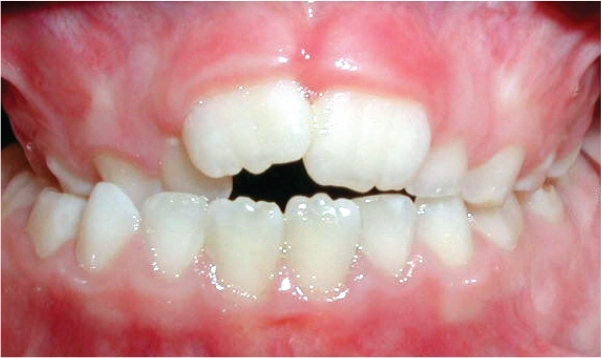

Anterior Crossbite

Malocclusions, like those illustrated above, may benefit from early diagnosis through full orthodontic examination.